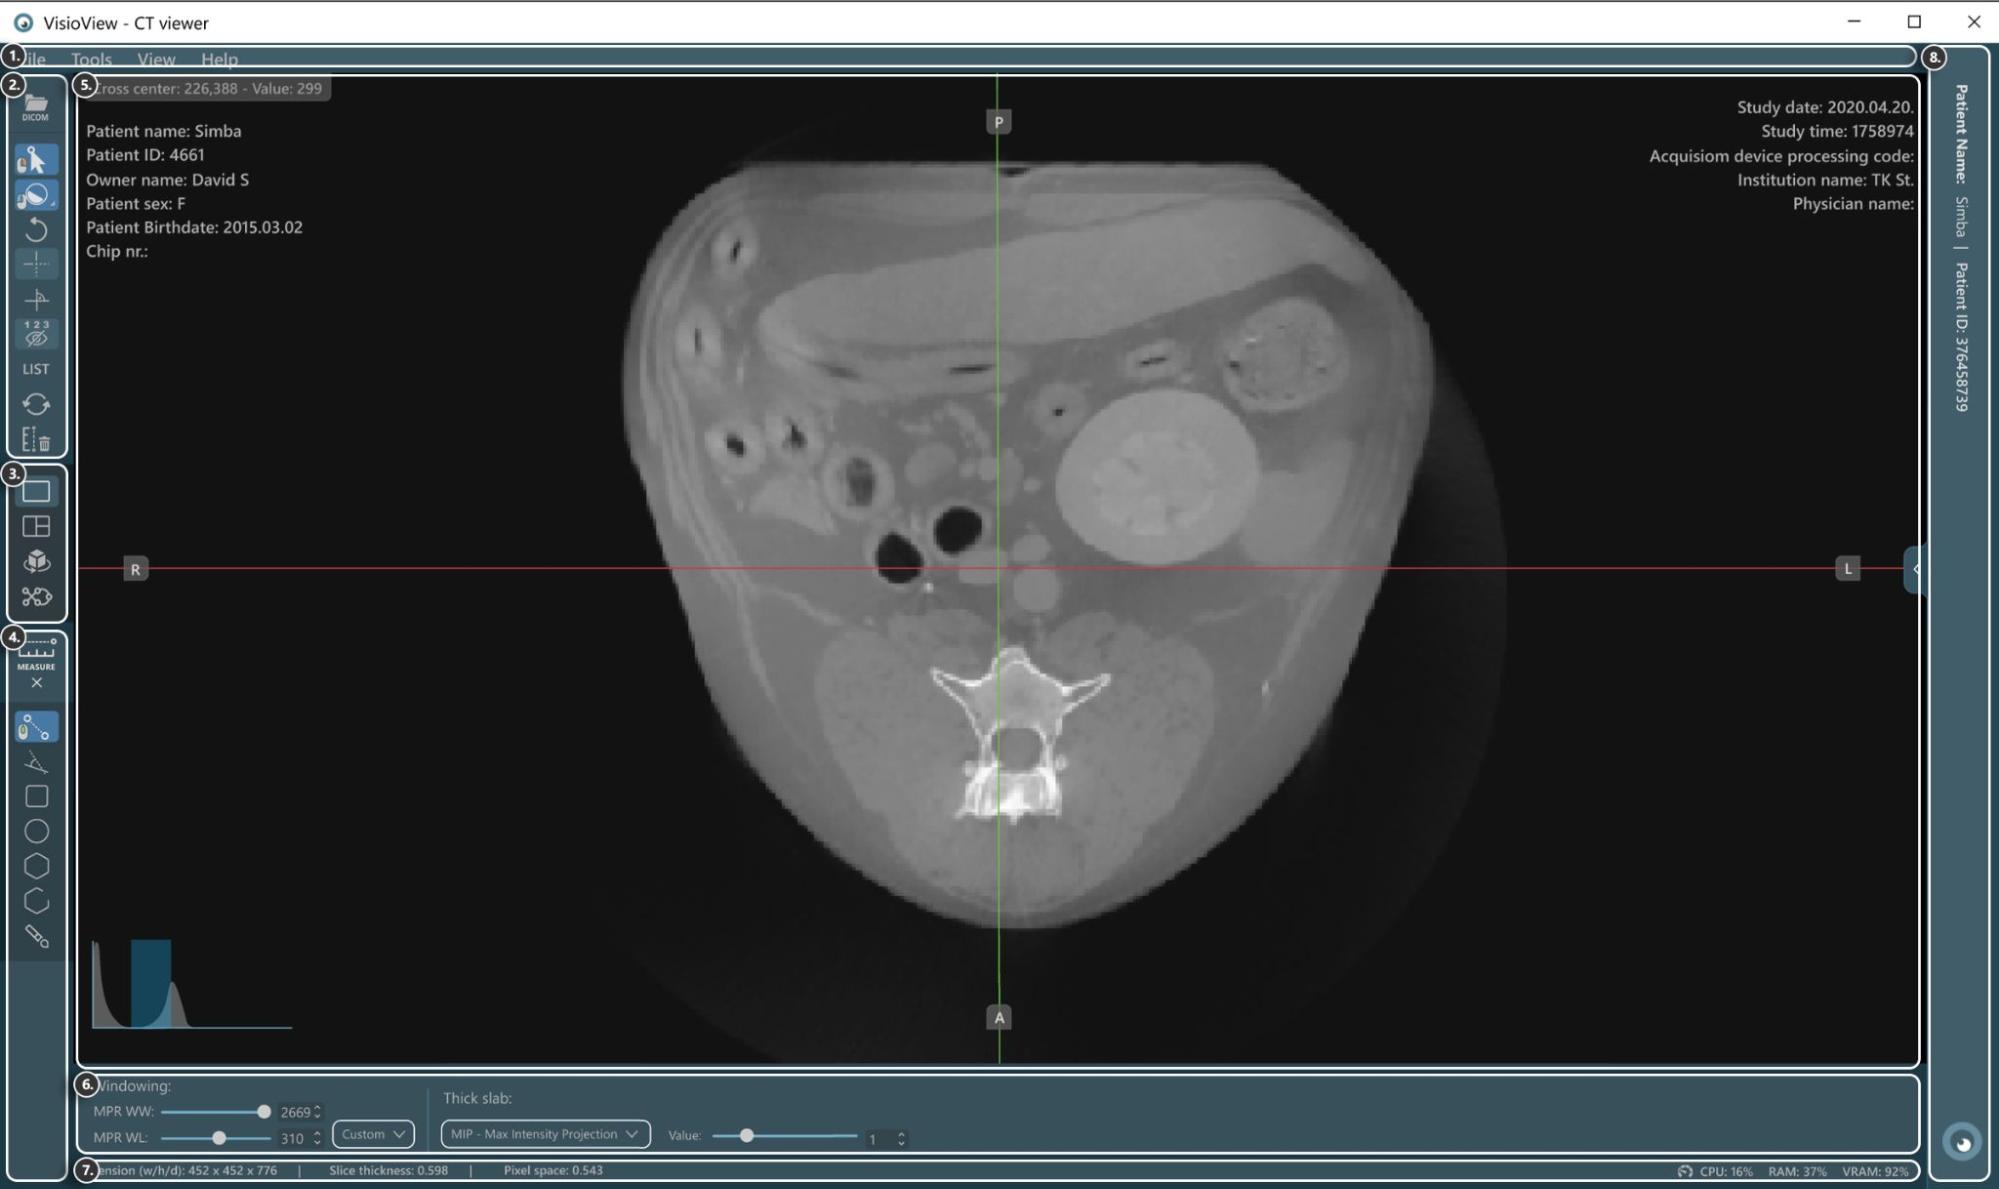

Sections of the VisioVIEW CT Viewer¶

The VisioVIEW CT Viewer consists of several sections, each tailored to a specific purpose. Below is a detailed description of each section.

Tools and Options¶

View Selector¶

Measurement Tools¶

Viewer Area¶

View Settings and Options¶

Information Bar¶